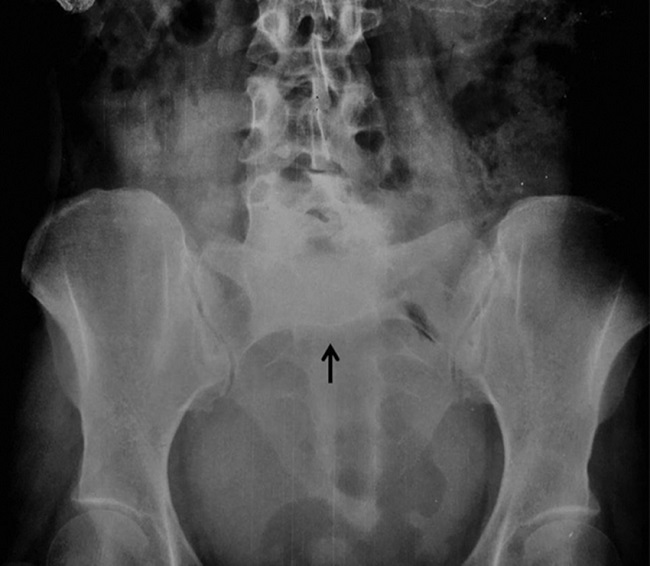

El signo del sombrero de Napoleón invertido se visualiza en las radiografías frontales de la columna vertebral lumbosacra. Representa una grave luxación del cuerpo de L5 sobre S1, sobrepasándolo y generando así la superposición de estructuras con la consecuente formación del sombrero1. Este signo radiológico fue descrito por primera vez en 1946, en un artículo publicado por Garland y Thomas, por su similitud con el conocido sombrero napoleónico2 (Figs. 1 y 2).

El “borde” o base del sombrero está formado por la rotación hacia abajo de los procesos transversales, y la “cúpula” del sombrero está formada por el cuerpo de L5, desplazado y caído, denominándose este proceso “espondilolistesis grave” o “espondiloptosis” (1.

La visualización del signo del sombrero invertido de Napoleón denota espondilolistesis grave o espondiloptosis de L5 sobre S1. Es importante reconocerlo, ya que se puede hallar incidentalmente en radiografías de frente de columna lumbosacra solicitadas por otro motivo, sin siquiera sospechar esta afección, y acompañarla de la incidencia de perfil para confirmar el desplazamiento del cuerpo vertebral.